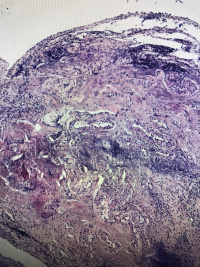

鼻息肉

性别

女

年龄

27

临床诊断

一般病史

鼻窦炎

标本名称

大体所见

灰白碎组织,大小3.2✖️2.4✖️0.5cm,部分成囊状

鼻粘膜息肉。